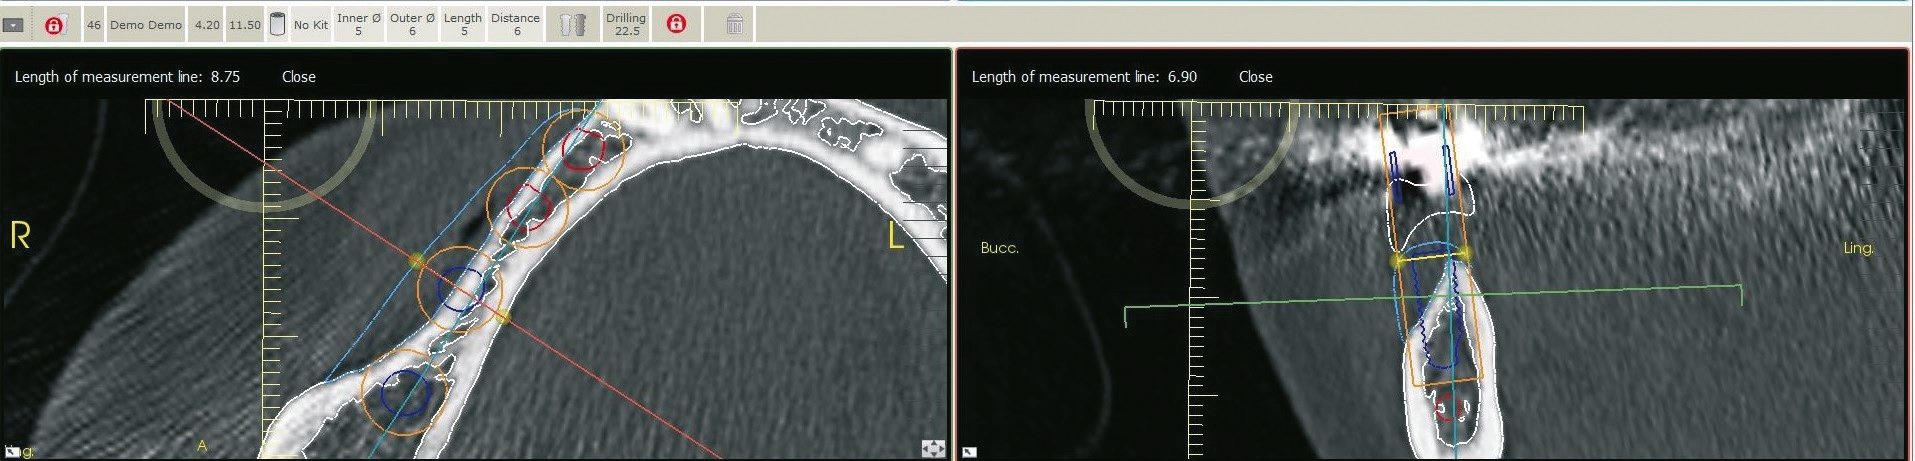

Eine 42 Jahre alte Frau stellte sich mit dem Wunsch nach einer festsitzenden prothetischen Versorgung im Unterkiefer vor. Die Voruntersuchung und die Röntgenaufnahmen zeigten eine Atrophie des Unterkiefers und damit ein für das Setzen von Implantaten eingeschränktes ortsständiges Knochenangebot (Abb. 1 und 2). Der Patientin wurden verschiedene Behandlungsoptionen für ein zweizeitiges GBR-Verfahren vorgestellt, um eine ausreichende Kammbreite für die anschließende Implantatbehandlung zu erhalten. Die Patientin lehnte ein Augmentationsverfahren mit autologem Knochentransplantat ab. Der vereinbarte Behandlungsplan beinhaltete letztendlich einen Knochenaufbau mit einem individuell konstruierten, gefriergetrockneten CADCAM-Allograft (maxgraft® bonebuilder, botiss biomaterials GmbH) und die anschließende Implantation von Straumann® BLX Roxolid® SLActive® Implantaten.

Der Lappen wurde reponiert und mit nicht resorbierbarem Nahtfaden der Stärke 4.0 adaptiert. Um einen spannungsfreien Wundverschluss zu erreichen, wurde apikal eine laterale Matratzennaht gesetzt. Die Nähte wurden nach 14 Tagen entfernt. Nach sechs Monaten komplikationsfreier Wund- und Einheilung kam die Patientin zur Implantatbehandlung erneut in die Praxis (Abb. 6 und 7). Beim Re-Entry wurden die Befestigungsschrauben entfernt, und es wurde eine Knochenkernbiopsie für die histologische Analyse entnommen (Abb. 8 und 9). Die histologische Untersuchung der mit Hämatoxylin-Eosin eingefärbten Schnittpräparate der Probe zeigte den laufenden Umbauprozess des FDBA-Blocks. Die histologische Aufnahme (Abb. 10) zeigte neu gebildeten Geflechtknochen (WB) in engem Kontakt mit dem Allograftmaterial (*) und umgeben von Bindegewebe (CT) und belegte die durch das Allograftmaterial vermittelte Knochenregeneration. Nach Bestimmung der geeigneten Implantatpositionen wurden in regio 47, 46 und 44 drei Bone Level Implantate Straumann® BLX Roxolid® SLActive ® mit einem Durchmesser von 4,5 mm und einer Länge von 10 mm gesetzt (Abb. 11 bis 14). Die Implantate wurden mit RB Verschlusskappen verschlossen, der Wundverschluss erfolgte mit Nahtmaterial der Stärke 4.0 (Abb. 15 und 16).